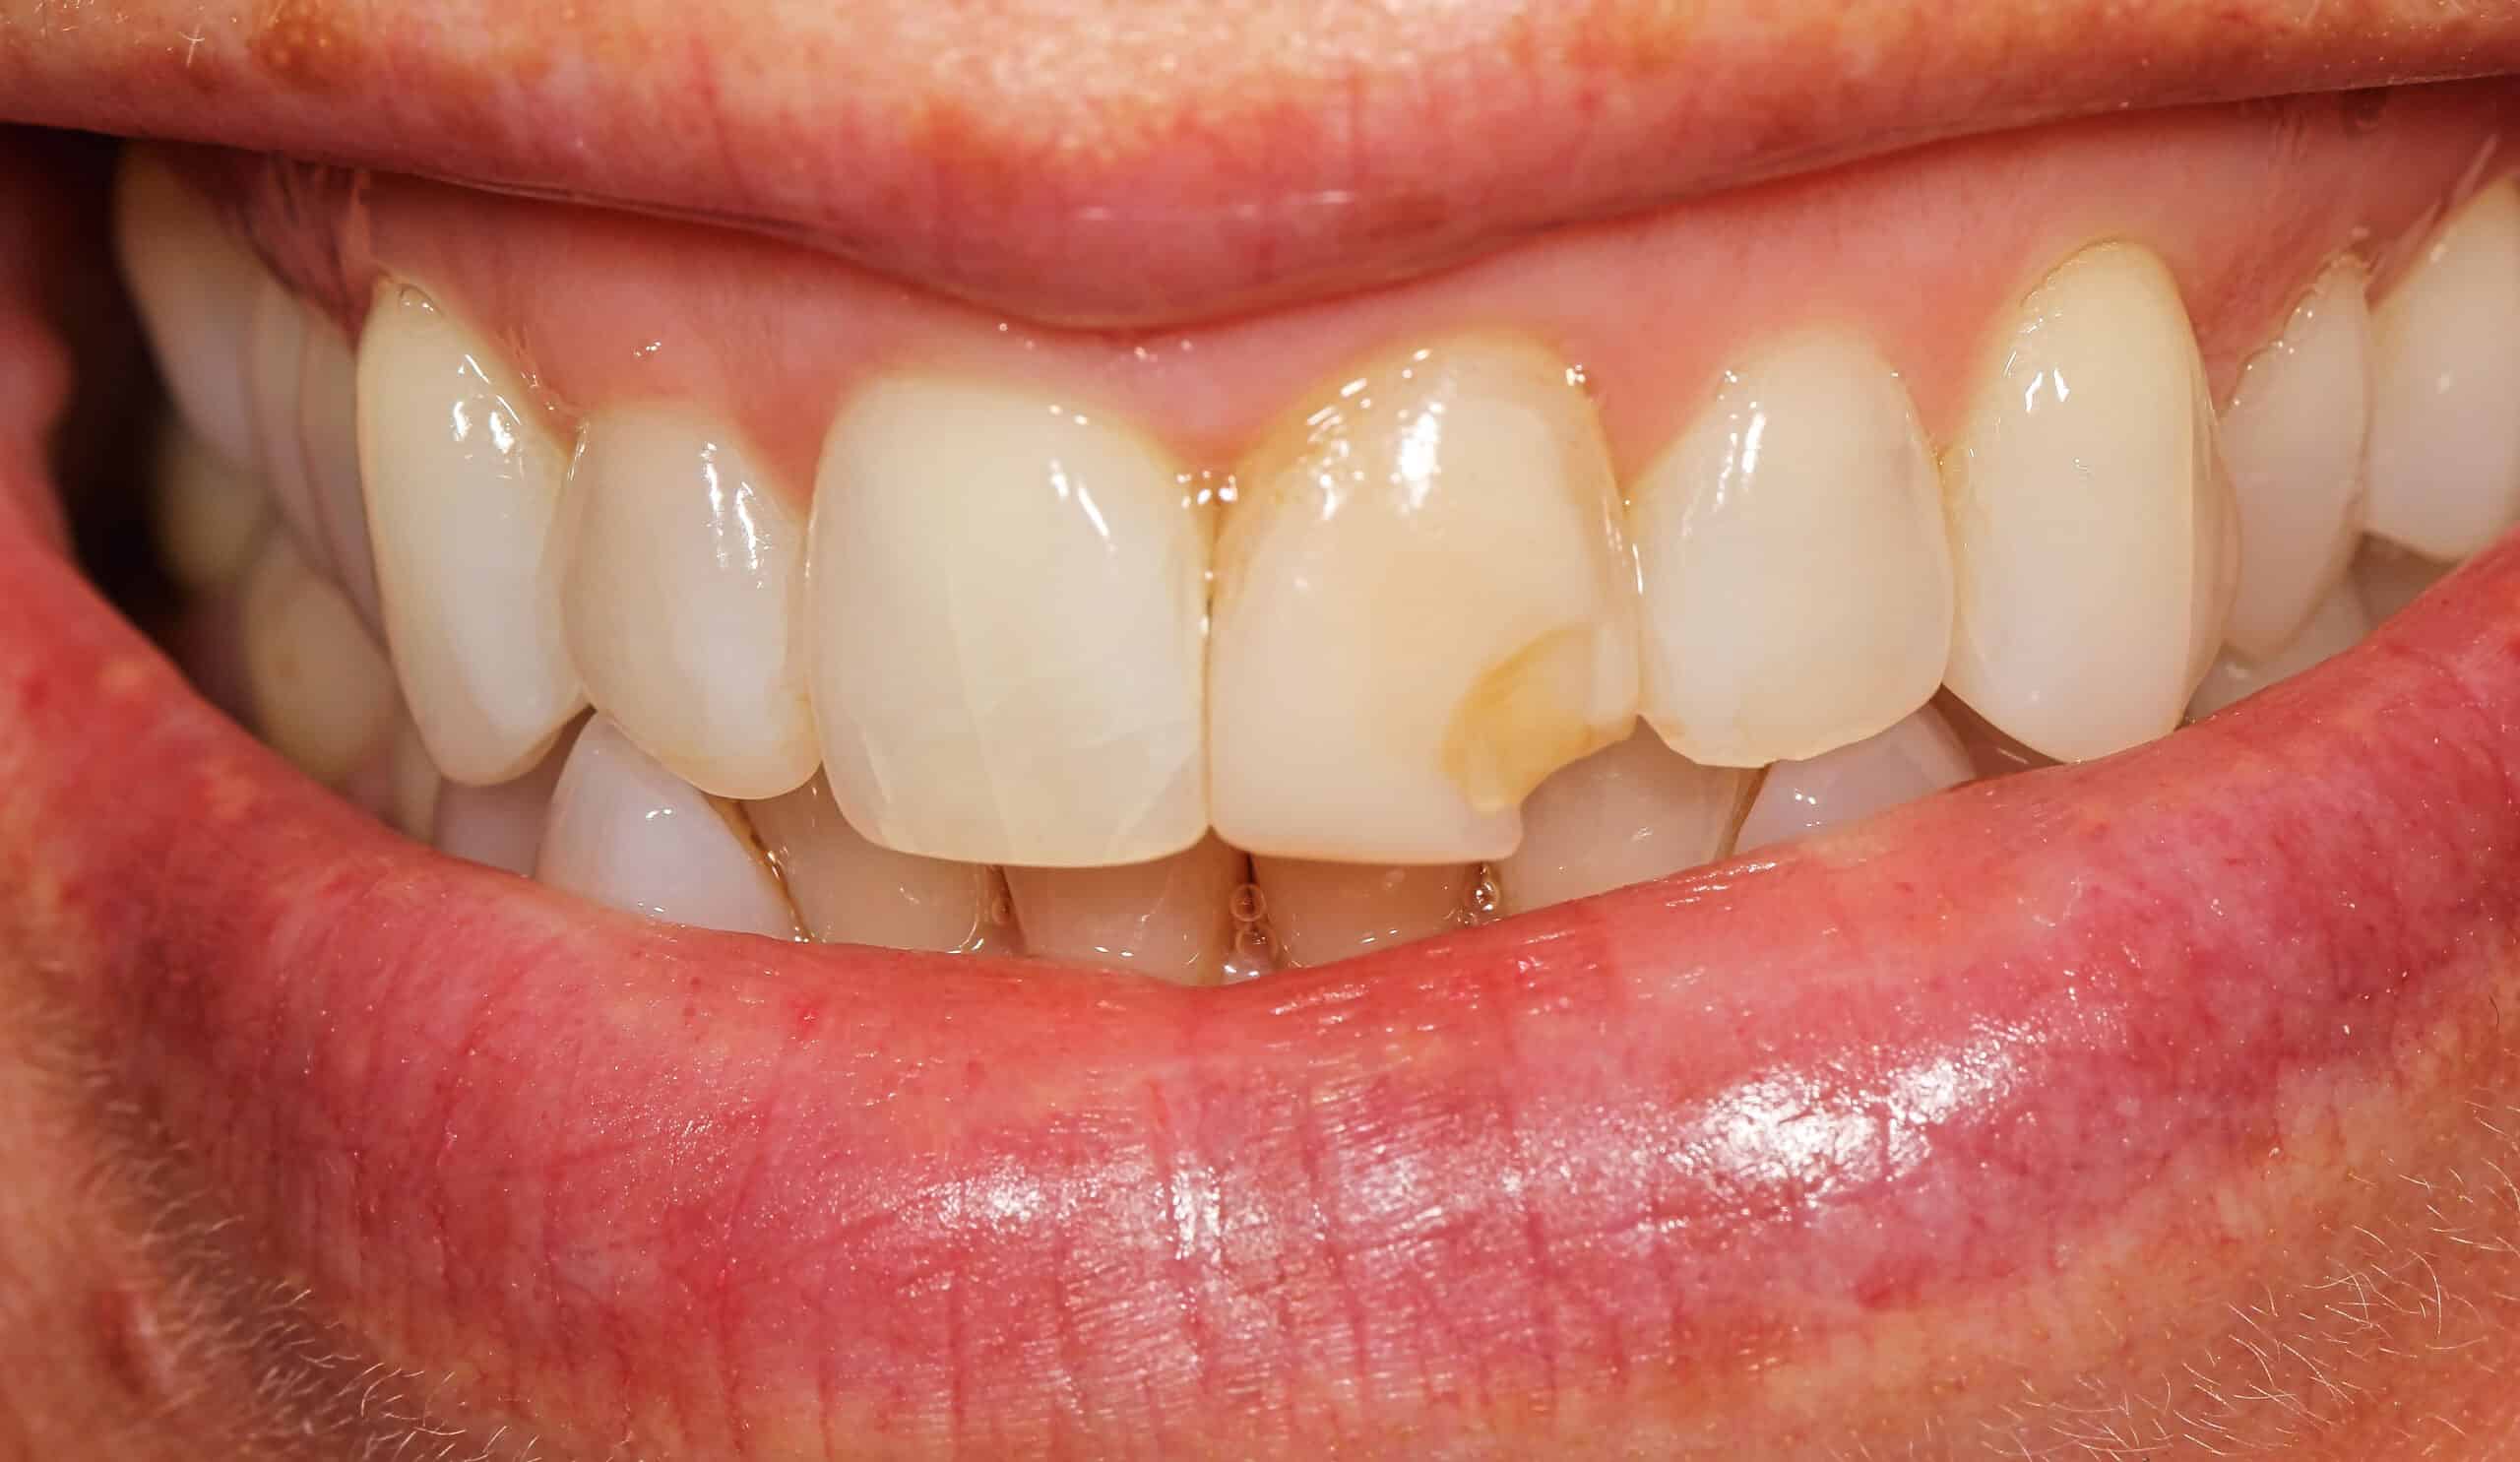

Our patient is a well known actress/comedian who accidentally broke her tooth while eating over the weekend. The dentist, Dr. Peter Mann, repaired her tooth with a bonding. In the future we recommend to place porcelain veneers on her two front teeth. Porcelain veneers will look much better and last longer than the bonding.